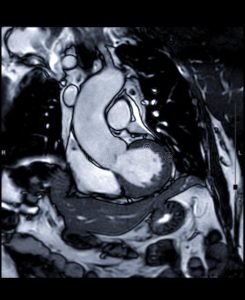

Le tecnologie avanzate che salvano la vita. Cardio RM senza e con contrasto: studiare le strutture cardiache con grande precisione